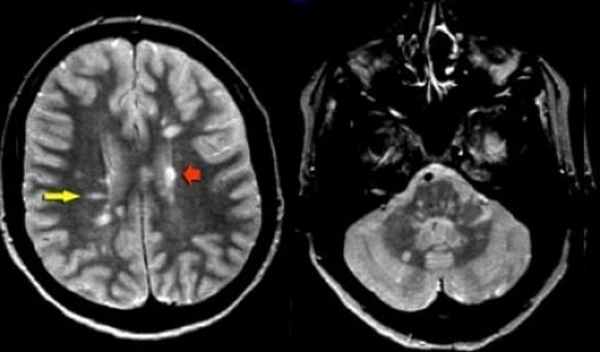

Как распознают рассеянный синдром на снимках? При рассеянном склерозе на снимках заметно характерно типичное распределение очагов в белом веществе головного мозга. Кроме того, для данного диагноза характерно поражение мозолистого тела, дугообразных волокон, височных долей, мозгового ствола, мозжечка и спинного мозга. Такое распределение очагов нехарактерно для иных патологических процессов, поэтому трудностей при постановке диагноза обычно не возникает. При ангиопатии возможны поражения ствола мозга, однако они обычно симметричны и располагаются центрально, в то время как очаги при рассеянном склерозе локализованы по периферии.

Признаки рассеянного склероза на МРТ головного мозга манифестируют себя следующим образом:

- появлением новых очагов и увеличением старых;

- во время обострения проведение МРТ головы с контрастом будет приводить к тому, что очаги демиелинизации будут накапливать контраст причудливым кольцевым способом.

На изображениях, получаемых посредством МРТ при рассеянном склерозе, диагност четко видит:

- более интенсивный сигнал, что на картинке выражено наличием очага или очагов

- общее количество очагов

- расположение очагов и их близость к важным структурам головного мозга.

Основные признаки РС:

- Обнаружение очагов демиелинизации в церебральных структурах является безусловным подтверждением диагноза PC.

- При спинальной форме PC на МРТ головного мозга выявляются множественные церебральные очаги, даже при минимальных клинических симптомах поражения головного мозга.

- Наиболее характерными MP-критериями стволовой формы PC является визуализация активных очагов в стволовых структурах, выраженные атрофические изменения и расширение ликворных цистерн.

- При ремиттирующих формах РС на ранних этапах отмечается наличие большего количества очагов крупных размеров, локализующихся в функционально значимых анатомических структурах, включающих ствол, мозжечок. На ранних сроках заболевания при этом типе течения наблюдается расширение желудочков и субарахноидальных цистерн.